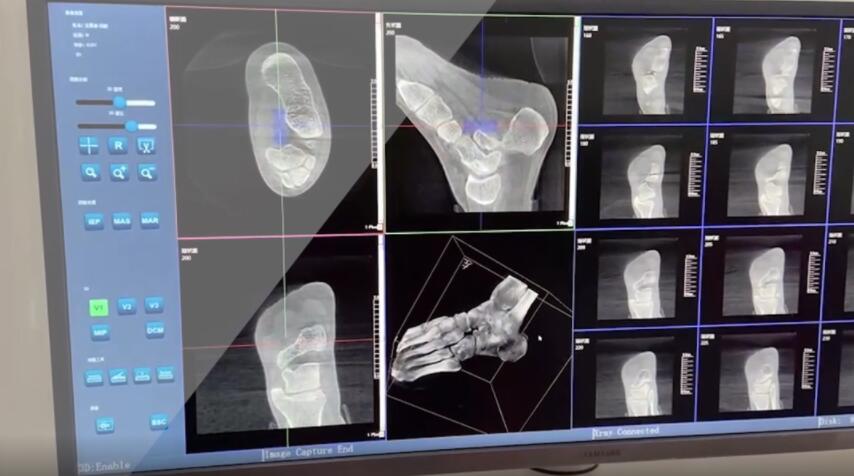

在術(shù)前,我們需要做三維掃描的CT檢查,我們必須要有CT的片子,還要有三維的重建。

在術(shù)中,我們怎么去判斷關(guān)節(jié)面平不平整呢?常規(guī)的正側(cè)位影像是不能判斷的。有些醫(yī)生為了準(zhǔn)確的判斷,可能會選擇做開放性的手術(shù),把關(guān)節(jié)暴露出來,在眼睛的直視下判斷關(guān)節(jié)面平不平整。但是關(guān)節(jié)全部打開,無疑增加了病人的創(chuàng)傷,而且增加了患者的恢復(fù)時間。所以如果在術(shù)中我們有三維影像的支持,對醫(yī)生做手術(shù)而言就會事半功倍,而且能夠大大的增加手術(shù)準(zhǔn)確度,增加患者術(shù)后的預(yù)后。所以在術(shù)中有三維影像的支持是非常必要的!